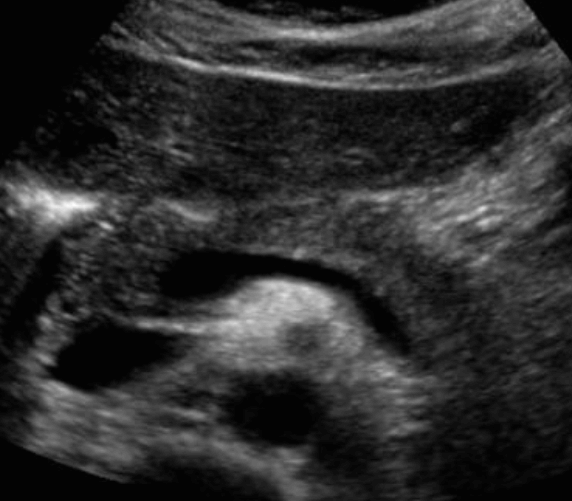

췌장과 주변 혈관들과의 관계 (pancreatic vascular and ductal landmarks)

췌장은 후복막강 장기로 주변 장기에 의해 영향을 많이 받아 초음파적으로 찾기 힘들기 때문에 주변혈관을 landmark로 찾아야 한다.

① 하대정맥 (IVC)

인체의 정중선에서 우측에 있고 췌장 두부의 바로 뒤쪽에 위치한다. 췌두부의 종괴는 하대정맥을 압박하거나 폐색 할 수도 있다.

② 대동맥(Aorta)

인체의 정중선의 좌측에 있고 췌체부와 상장간막동맥 뒤에 위치한다.

③ 상장간막정맥(SMV)

비장정맥과 이어져 있고 구상돌기(uncinate process) 앞에 있다.

④ 상장간막동맥(SMA)

췌장 체부의 뒤쪽과 대동맥의 앞쪽에 위치한다.

⑤ 비동맥(Splenic artery)

췌체부의 위쪽 췌미부의 뒤쪽에 위치하고 비문(splenic hilum)으로 들어간다.

⑥ 비정맥(Splenic vein)

췌장 뒤에 위치하여 상장간막정맥(SMV)과 만나 간문맥(portal vein)을 형성한다.

⑦위십이지장동맥(Gastroduodenal artery)

췌두부의 앞쪽으로 지나간다

⑧원위 담관(Distal CBD)

하대정맥 앞쪽에 있고 췌두부의 뒤쪽을 관통하여 십이지장으로 들어간다.

정상췌장의 초음파적 소견

췌장은 막이 없는 장기로 초음파상 경계면이 확실하지 않다. 췌장의 에코는 간보다 약간 밝거나 같으며 균질하다. 나이가 증가하면서 위축되고 지방침착으로 인해 췌장 실질이 밝아진다. 주췌관의 직경은 3mm 이상이면 확장으로 보나 분단위로 수축과 확장을 반복하여 변하기 때문에 시간에 따라 확인해야 한다. 실제검사에서 대칭성의 소실, 외곽선의 급격한 변화, 에코변화등을 주의 깊게 관찰해야 한다.